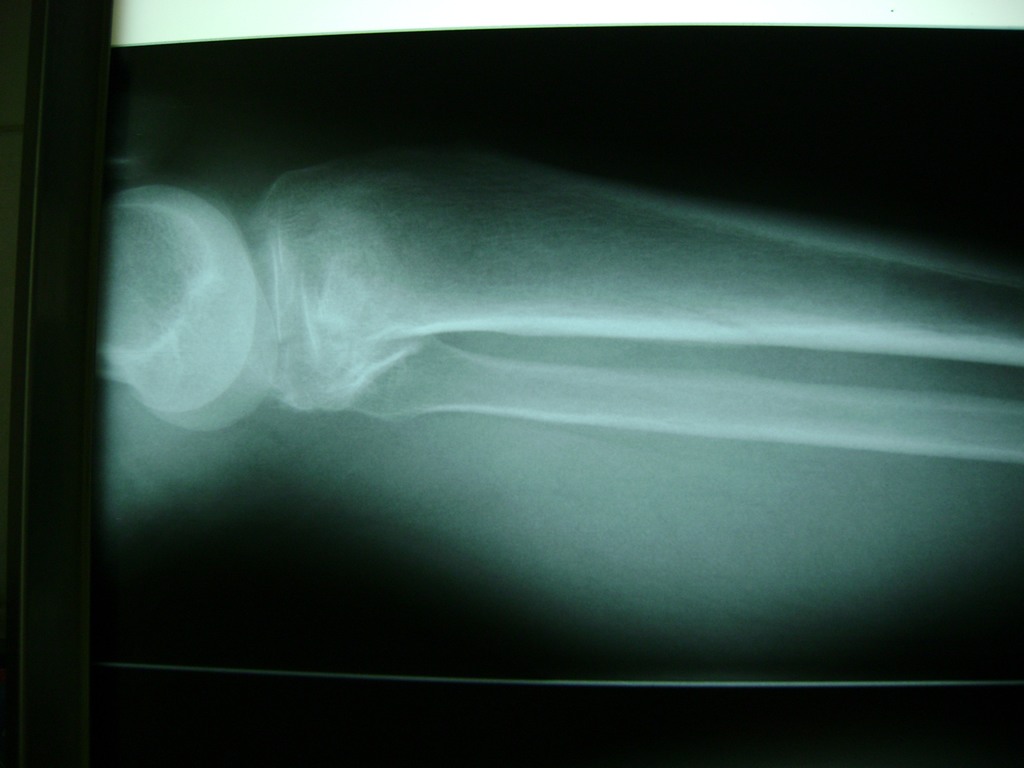

Cirugías de Peroné y Tibia